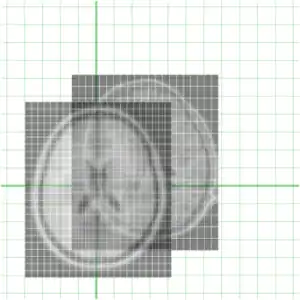

To get an idea of how they currently overlay I have put them together below

Clearly they are not aligned or "registered" to each other so we have to use a tool such as minctracc or mritoself in order to align them as such: